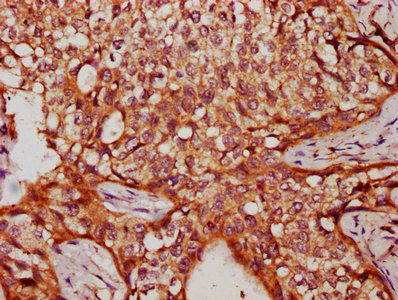

IHC image of CSB-PA735951LA01HU diluted at 1:300 and staining in paraffin-embedded human cervical cancer performed on a Leica BondTM system. After dewaxing and hydration, antigen retrieval was mediated by high pressure in a citrate buffer (pH 6.0). Section was blocked with 10% normal goat serum 30min at RT. Then primary antibody (1% BSA) was incubated at 4°C overnight. The primary is detected by a biotinylated secondary antibody and visualized using an HRP conjugated SP system.